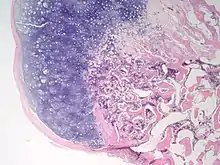

![]() | Tuberculoid leprosy | Skin biopsy showing multiple peri-appendageal granulomas. | Category: Histopathology of leprosy | Leprosy |